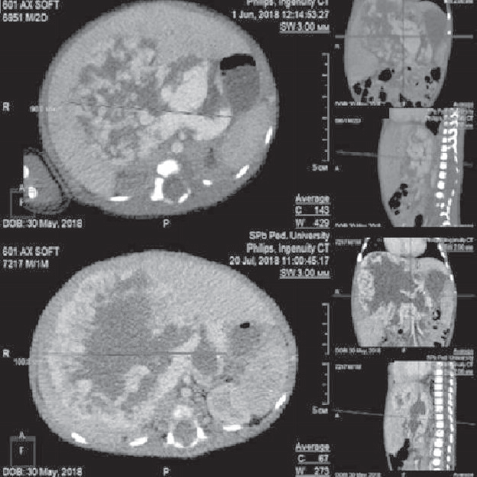

Hemangiomas are the most frequent tumors of childhood age. In the first year of life their prevalence is 10–12%. Among premature children, the prevalence of hemangiomas correlates with the degree of prematurity. Liver hemangiomas are a wide range of benign vascular formations that can acquire both malignant course and capable of spontaneous regression. Small-sized hemangiomas generally do not require specific treatment and proceed asymptomally. Large-sized formations can cause life-threatening conditions such as severe thrombocytopenia with coagulopathy (Kazabah–Merrit syndrome), anaemia, tumor hemorrhage, spontaneous and traumatic tumor breaks, heart failure associated with intra-tumor bypass of blood flow, abdominal compression syndrome, severe hypothyroidism. Diagnosis of this pathology is carried out on the basis of a set of data of medical imaging, laboratory diagnostics and clinical picture. This review presents key points of general classification, the most characteristic diagnostic signs, as well as basic algorithms of treatment of liver hemangiomas in newborns and children of the first year of life. There are also described 2 clinical cases of newborns with giant liver hemangiomas, which were examined and treated in the pathology department of newborns and infants of Perinatal Center of St. Petersburg State Pediatric Medical University with a description of the peculiarities of the course of each of them.